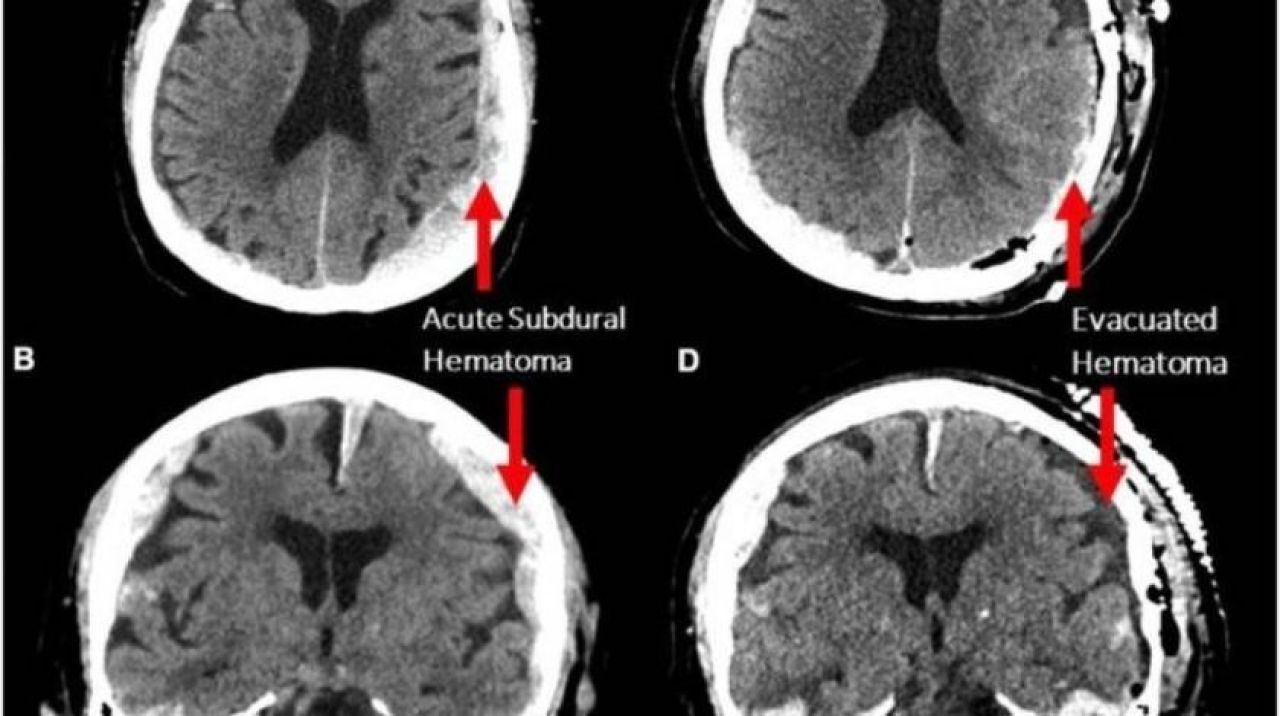

Bu kapsamda 87 yaşındaki bir epilepsi hastasının kalp krizi geçirmesinin ardından ölümünün gerçekleştiği sırada kayıtta olan Elektroensefalografi (EEG) sayesinde beyin hareketliliği incelendi.